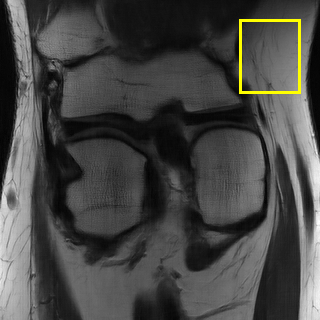

We also provide visual comparisons in Fig. 7- 9. According to these images, we can see that EAMRI has fewer bright dots in the heatmaps and more clearer and accurate edges in the zoomed-in areas. The above quantitative and qualitative analysis fully demonstrate the effectiveness of the proposed EAMRI. Due to the page limit, more visual comparisons can be found at https://github.com/MIVRC/EAMRI.

(a)

(b)

(c)

(d)

(e)

(f)

(g)